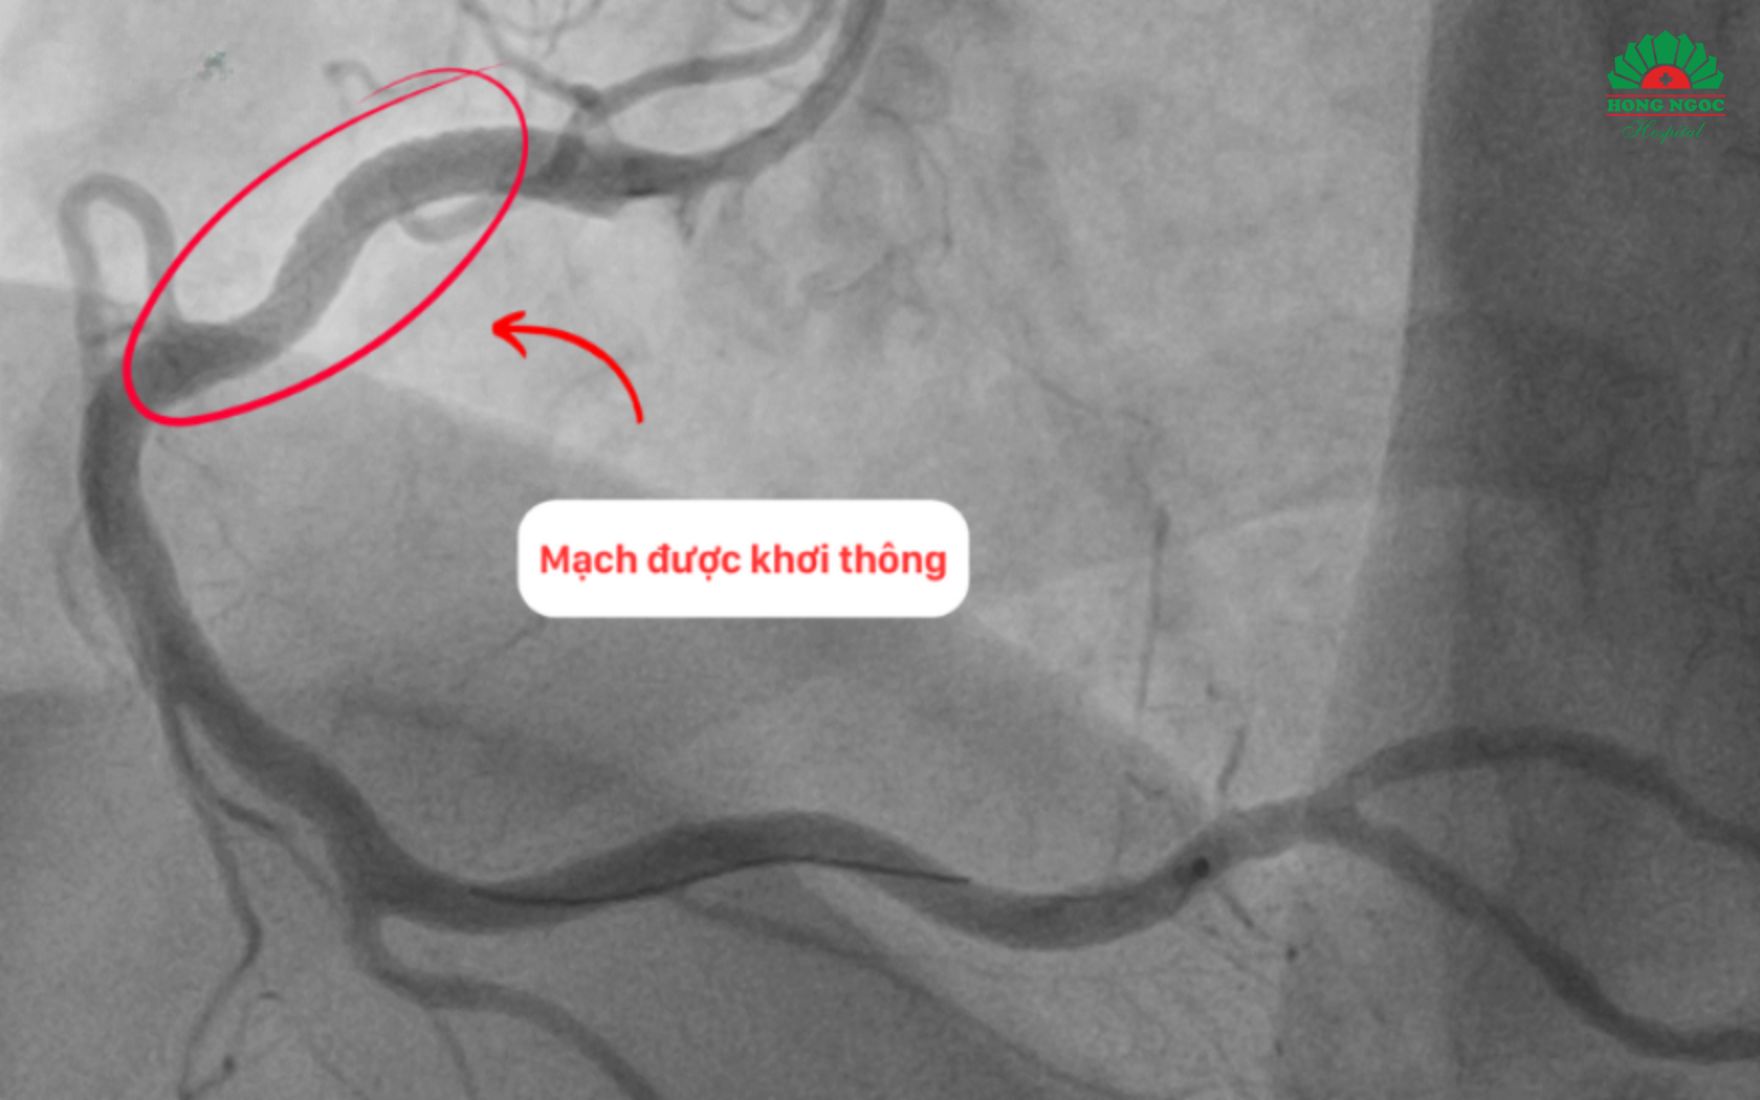

Với chiến lược nhanh chóng và thao tác cẩn trọng ê kíp đã hút được rất nhiều cục máu đông ra khỏi mạch vành, mở đường cho việc đặt thành công 01 stent đường kính 4.0mm và dài 28mm giúp khơi thông dòng máu nuôi tim, ngăn chặn phần cơ tim bị hoại tử lan rộng.

Thành công đặt 01 stent kích thước 4.0 x 26 mm